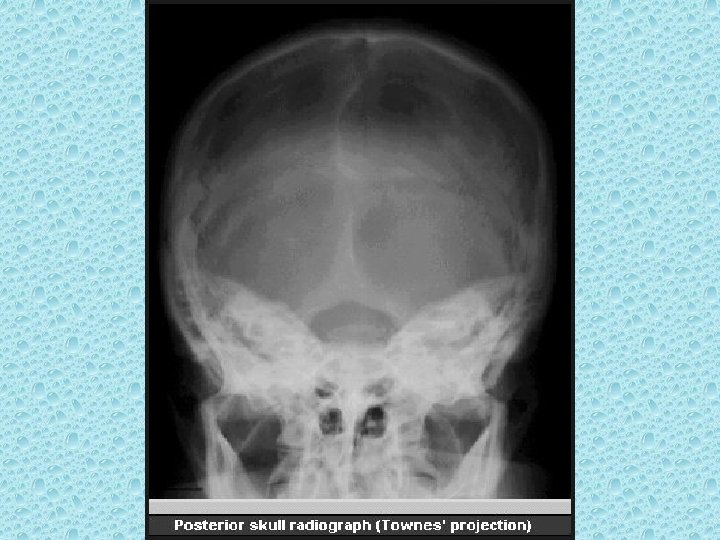

BAŞ-YÜZ RADYOLOJİK ANATOMİSİ

KRANYAL KEMİKLER • • • Paryetal (2) Frontal Oksipitai Temporal (2) Sfenoid Etmoid

KRANYAL SÜTÜRLER • Koronal (Paryetal-frontal arasında) • Sagital (iki paryetal arasında) • Lambdoid (paryetal, temporal ile oksipital arasında) • Skuamoz (Paryetal-temporal arasında)